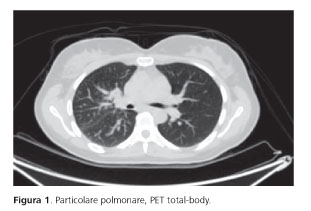

Nel giugno 2019 una donna di 43 anni in condizioni generali compatibili con Performance Status 0 secondo Eastern Cooperative Oncology Group (ECOG), non fumatrice, si presenta in ambulatorio di Oncologia per eseguire una prima visita a seguito di un episodio di emottisi. Una RX torace dimostrava la presenza di un’opacità centrale destra. Una successiva TC toracica confermava la presenza di un addensamento polmonare al lobo medio, adenopatie mediastiniche e ilari omolaterali e una sospetta linfangite neoplastica. Veniva conclusa la stadiazione strumentale con PET total-body che documentava un interessamento linfonodale ad alcune stazioni N3 tra cui la sede retroclaveare, paraortica e latero-cervicale.

Infine una TC encefalica escludeva secondarismi a questo livello (figura 1).

Si concludeva per uno stadio clinico cT2N3M1a.